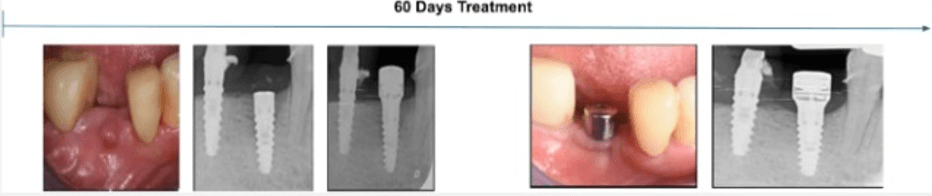

This case involved a patient diagnosed with inflammatory environment, treated in June 2024.

The surgical procedure included implantoplasty and guided bone regeneration, followed by the immediate placement of the MAGDENT Miniaturized Electromagnetic Device (MED) for a duration of 3 weeks. At the 3-week mark, after soft tissue stabilization, the final prosthesis was delivered.

The clinical outcome shown here represents a follow-up at 11 months (approximately 1 year) post-treatment. The site demonstrated excellent tissue healing, absence of inflammation, and radiographic bone stability, supporting the role of PEMF technology as a complementary approach in managing peri-implant defects.

Condition Treated: Severe Inflammatory environment with a measured Pocket Depth of 6mm.